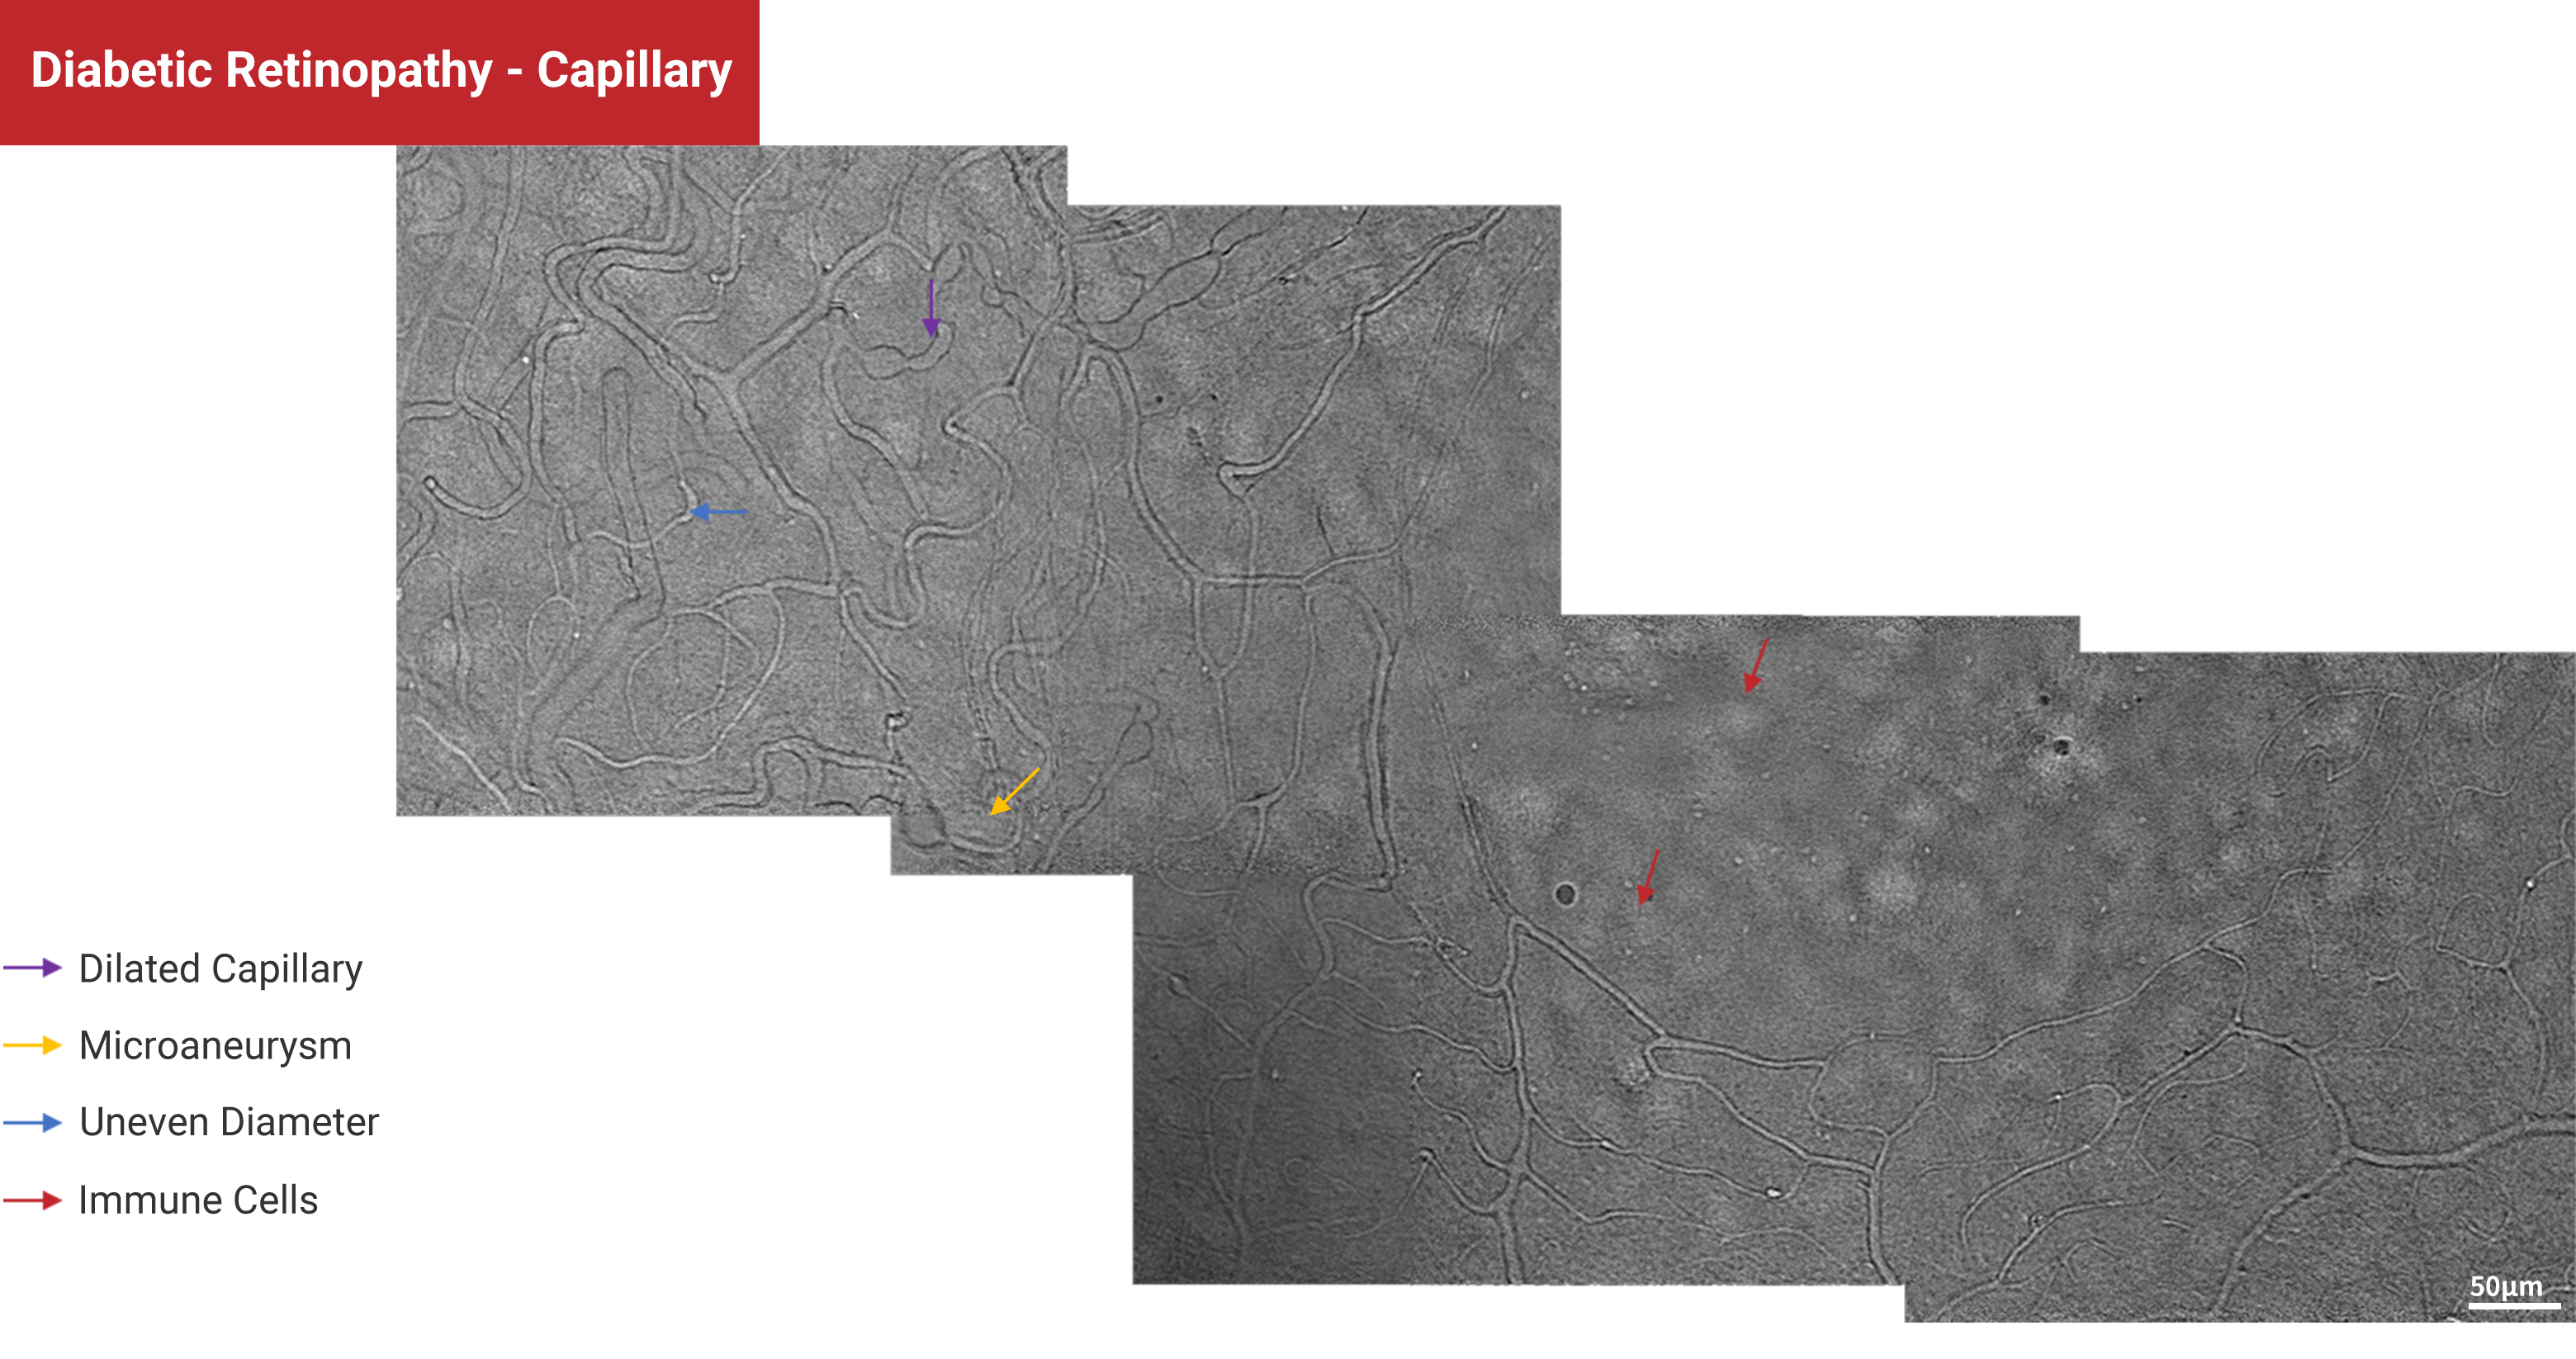

Diabetic Retinopathy - Capillary